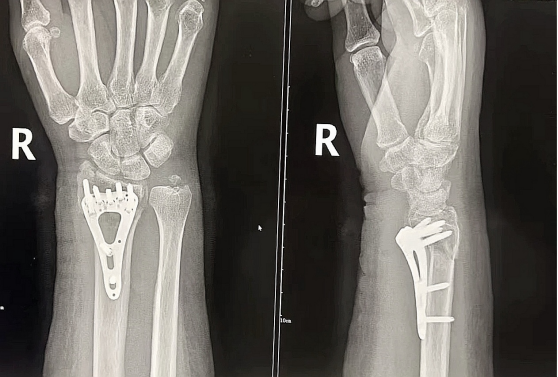

1. 骨骼肌肉系统:快速诊断骨折、关节脱位、骨质增生、骨肿瘤等问题,还能利用双能X线吸收法对椎体和髋关节进行骨密度测量,评估骨质疏松、预防骨折风险。